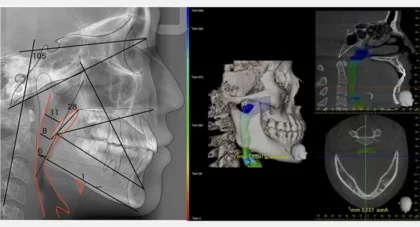

AIを活用した横顔のデジタル診断

当院では、AIを活用した独自のシミュレーションソフトにより、CTやセファロレントゲン、顔貌写真など多角的なデータを解析。

骨格や顔全体のバランスまで考慮した治療後の横顔変化を予測・可視化し、より精度の高い診断と治療計画を実現しています。見た目の美しさと機能性の両立を追求する矯正治療の核となる技術です。

VTO(Visual Treatment Objective)

治療後の骨格・歯列変化を予測できます。

モーフィング/横顔シミュレーション

治療後の横顔の変化をシミュレーションでご覧いただけます。矯正後のフェイスラインや口元のバランスを事前にイメージできるため、治療への安心感につながります。